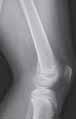

Rycina 17.81.

A, B – Genu recurvatum u pacjenta po złamaniu okolicy proksymalnej części chrząstki nasadowej piszczeli.

Rycina 17.82.

Uszkodzenie tętnicy podkolanowej wskutek złuszczenia nasady bliższej kości piszczelowej (S-H 1). Zagrożenie rozwojem zespołu przedziałów powięziowych jest poważne.